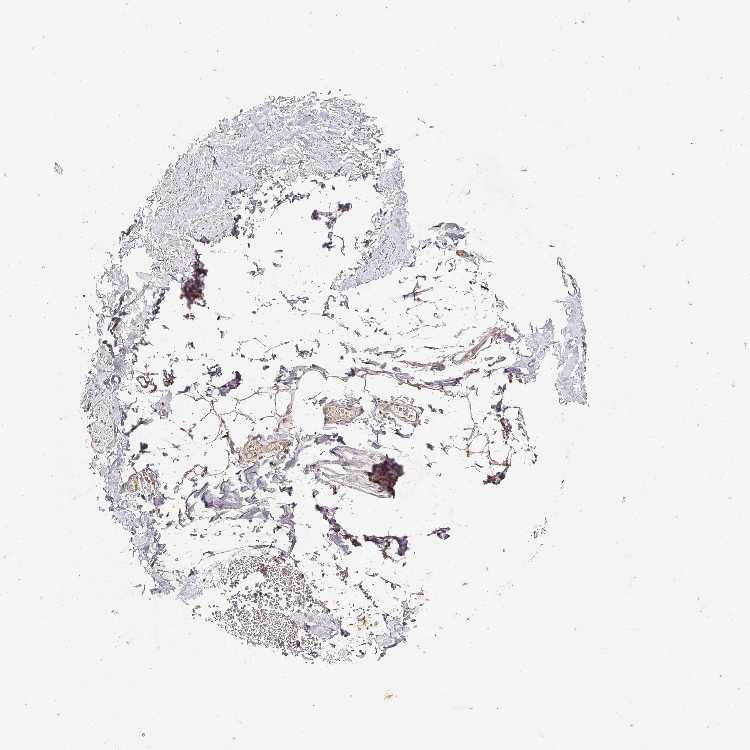

SOFT TISSUE 1 - Antibody stainingi

Antibody staining in the annotated cell types in the current human tissue is reported as not detected, low, medium, or high, based on conventional immunohistochemistry profiling in selected tissues. This score is based on the combination of the staining intensity and fraction of stained cells.

Each image is clickable and will lead to virtual microscopy that enables deeper exploration of all samples and also displays staining intensity scores, fraction scores and subcellular localization as well as patient and tissue information for each sample.

Antibody CAB033237

Fibroblasts Low

Peripheral nerve Low